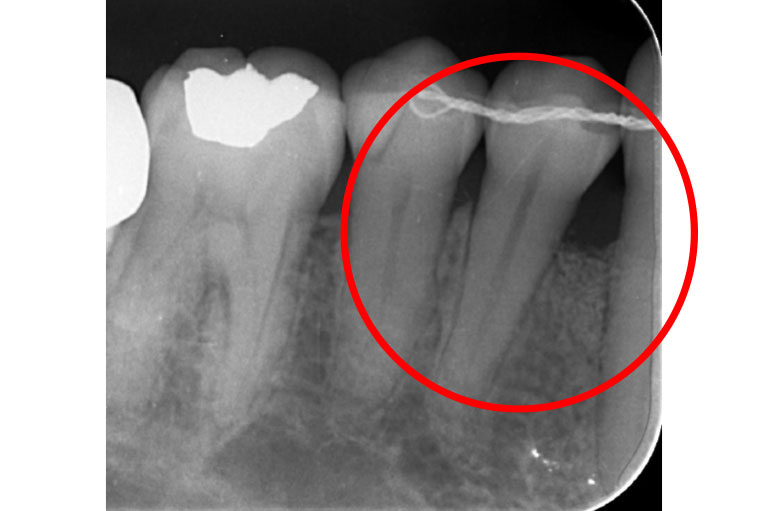

治療前

治療中

治療後

| 治療名 | 歯周組織再生療法 |

| 患者様情報 | 50代 女性 |

| 担当医 | 亀岡 聡貴 先生 |

| 費用 | 15.000円 (税込) 保険内 |

| 主訴 | 右下3番付近の歯茎が 1週間前から腫れている。 |

| 治療期間 | 1年 |

| 治療内容 | 歯周基本治療(SRP、TBI、咬合調整など)+歯周外科治療(再生療法)を行いました。全顎的に歯茎の炎症も落ち着き、レントゲン上でも骨の再生を認められました。 |

| 治療のリスク | 現在の状態の維持のため、継続的にメインテナンスを行う必要があります。 |